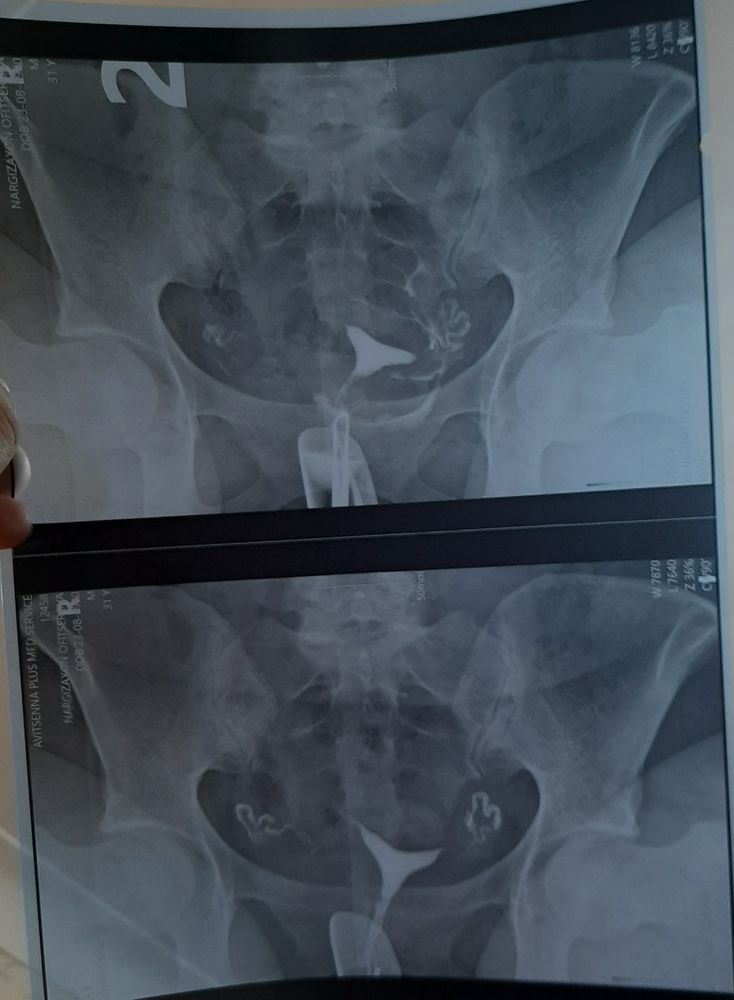

Изображение

Вот мой снимок